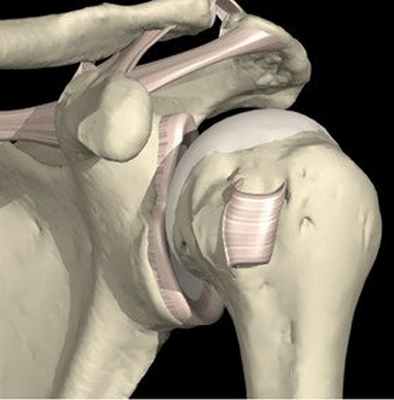

Плечевой сустав состоит из головки плечевой кости и суставной впадины лопатки и имеет наибольшую подвижность среди всех суставов человеческого тела. Это обеспечивается значительным несоответствием формы головки плечевой кости, которая имеет практически сферическую форму, и плоской впадиной лопатки (рис. 1).

Рис. 1 Левый плечевой сустав (вид спереди)

Соответствие суставных поверхностей плечевого сустава повышает суставная губа. Суставная губа является хрящеподобной структурой, которая прочно связана с лопаткой (рис. 2). Суставная губа повышает конгруэнтность головки плечевой кости и суставной впадины лопатки, является механическим барьером для соскальзывания головки плечевой кости с суставной впадины лопатки. К суставной губе прикрепляется капсула плечевого сустава.

Суставная губа плеча плече-лопаточные связки

Капсула сустава имеет в своем составе зоны утолщения. Это плече-лопаточные связки – верхняя, средняя и нижняя, впервые описанные известным ученым Галеном еще в средние века. Каждая из связок противостоит вывиху плеча при определенном угле отведения.

Таким образом, суставная губа и капсула сустава вместе с плече-лопаточными связками представляют анатомически и функционально единое целое, обеспечивающее значительный процент стабильности сустава. Если возникает отрыв суставной губы от впадины лопатки, утрачивается также стабилизирующая функция комплекса плече-лопаточных связок.